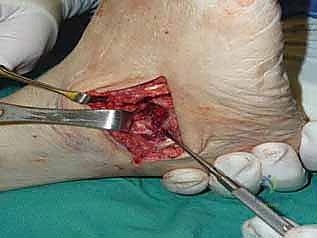

يتم إجراء شقين جراحيين للوصول إلى المفاصل الثلاثة:

* شق خارجي (Lateral Incision): للوصول إلى المفصل تحت الكاحل والمفصل العقبي المكعبي.

* شق داخلي (Medial Incision): للوصول إلى المفصل الكاحلي الزورقي.

يحرص الدكتور هطيف على حماية الأعصاب والأوعية الدموية الحساسة المحيطة بالمنطقة.

2. تحضير المفاصل وإزالة الغضاريف (Joint Preparation)

هذه هي الخطوة الأهم. باستخدام أدوات دقيقة، يتم كشط وإزالة جميع الغضاريف المتبقية (التالفة) من المفاصل الثلاثة وصولاً إلى العظم الإسفنجي النازف (Bleeding Subchondral Bone). يجب أن يكون العظم حياً وغنياً بالدم لضمان التئامه والتحامه مع العظم المقابل.